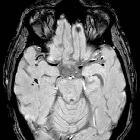

MRI

- stage 3 (brainstem): diffuse axonal injury lesions in the brainstem, almost invariably in addition to the lobar white matter and corpus callosum

- most common sites: dorsolateral midbrain, upper pons, and superior cerebellar peduncles

Diffuse axonal injury lesions were not clearly defined in this article by their MR appearance aside from being multiple, small, elliptical "lesions" located in characteristic areas of white matter. Small petechial hemorrhages, which appear hypointense on T2*-weighted images, are characteristic but represent a minority of true diffuse axonal injury lesions .